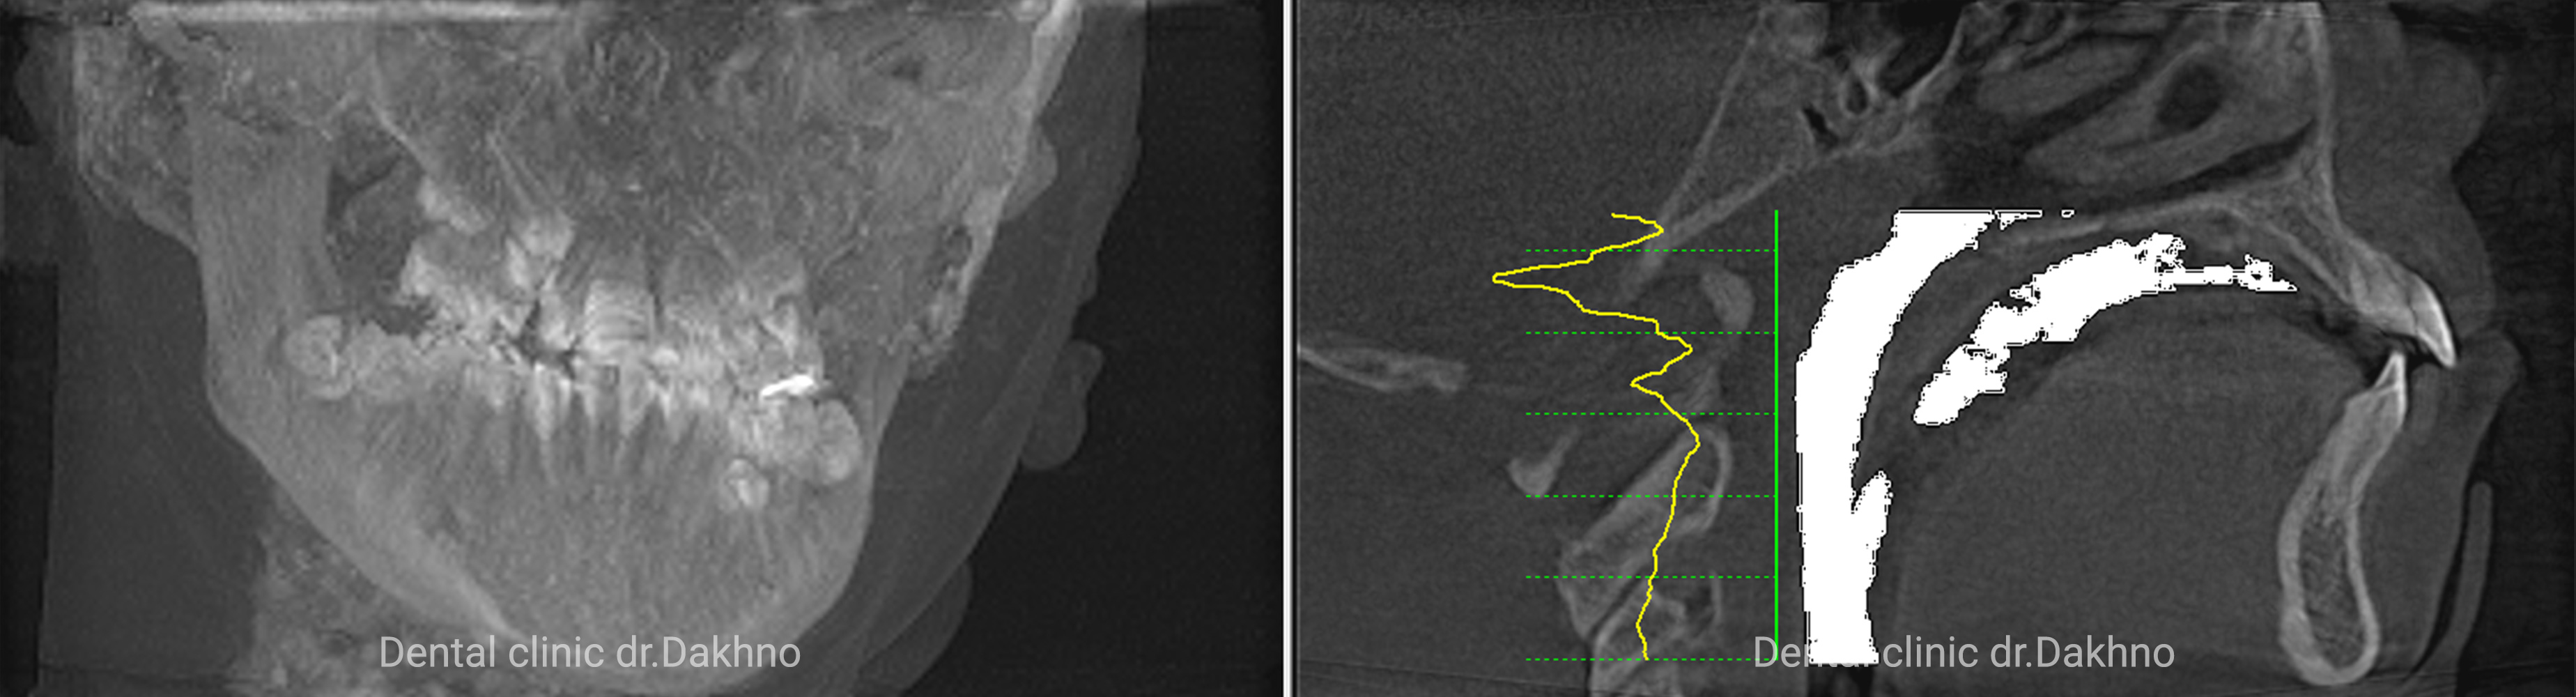

Клінічний діагноз: вертикальний тип росту і розвитку нижньої третини обличчя, бімаксілярна мікрогнатія, звуження і деформація зубних рядів верхньої і нижньої щелепи, скученість зубів.

Липень 2017 Батьки звернулися в клініку з метою виправлення скученості зубів. Після отримання необхідних діагностичних даних: виконання КПКТ (конусно-променевої комп’ютерної томографії), фотопротокола і отримання діагностичних моделей прийнято рішення першим етапом ортодонтичного лікування виконати розширення верхньої щелепи за рахунок фіксованого апарату HYREX на оклюзійних накладках.